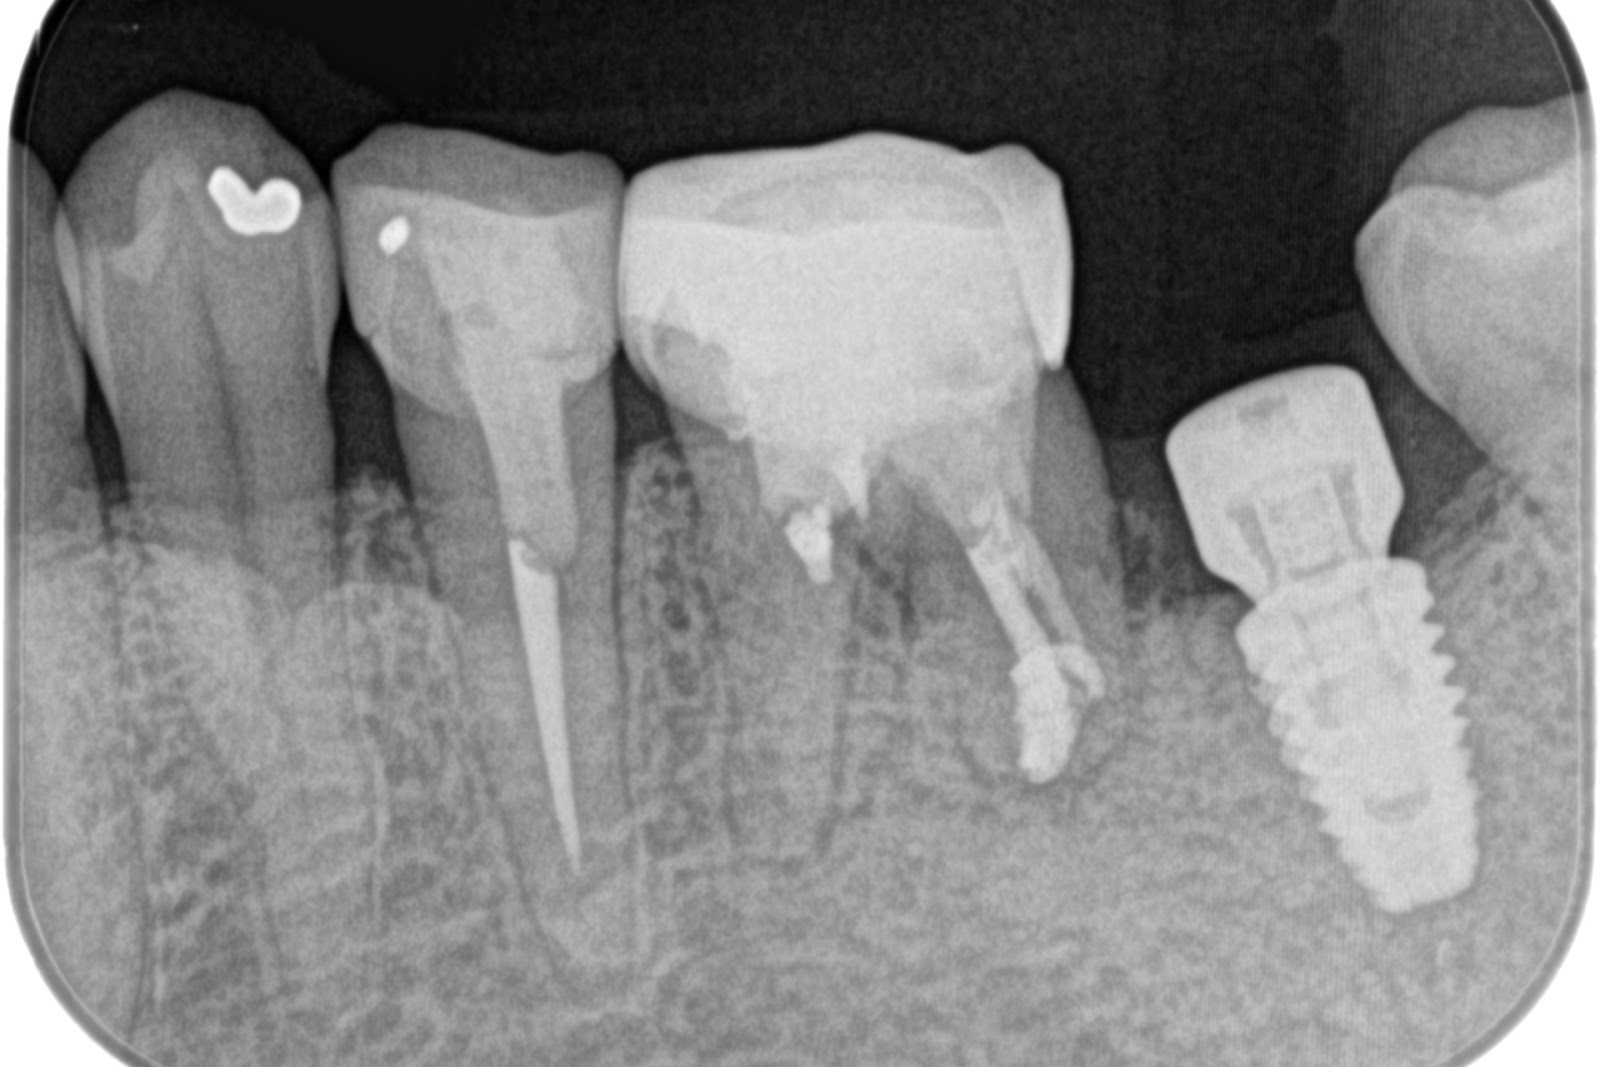

手術後(左下)

上部構造セット後(左下)